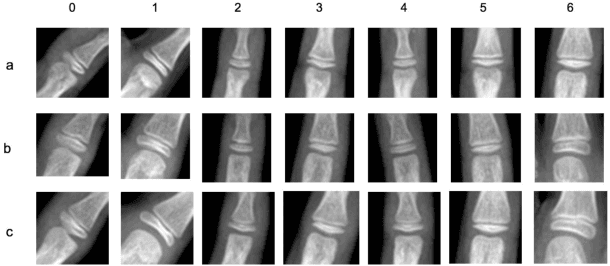

Abstract:Bone age assessment is an important clinical trial to measure skeletal child maturity and diagnose of growth disorders. Conventional approaches such as the Tanner-Whitehouse (TW) and Greulich and Pyle (GP) may not perform well due to their large inter-observer and intra-observer variations. In this paper, we propose a finger joint localization strategy to filter out most non-informative parts of images. When combining with the conventional full image-based deep network, we observe a much-improved performance. % Our approach utilizes full hand and specific joints images for skeletal maturity prediction. In this study, we applied powerful deep neural network and explored a process in the forecast of skeletal bone age with the specifically combine joints images to increase the performance accuracy compared with the whole hand images.